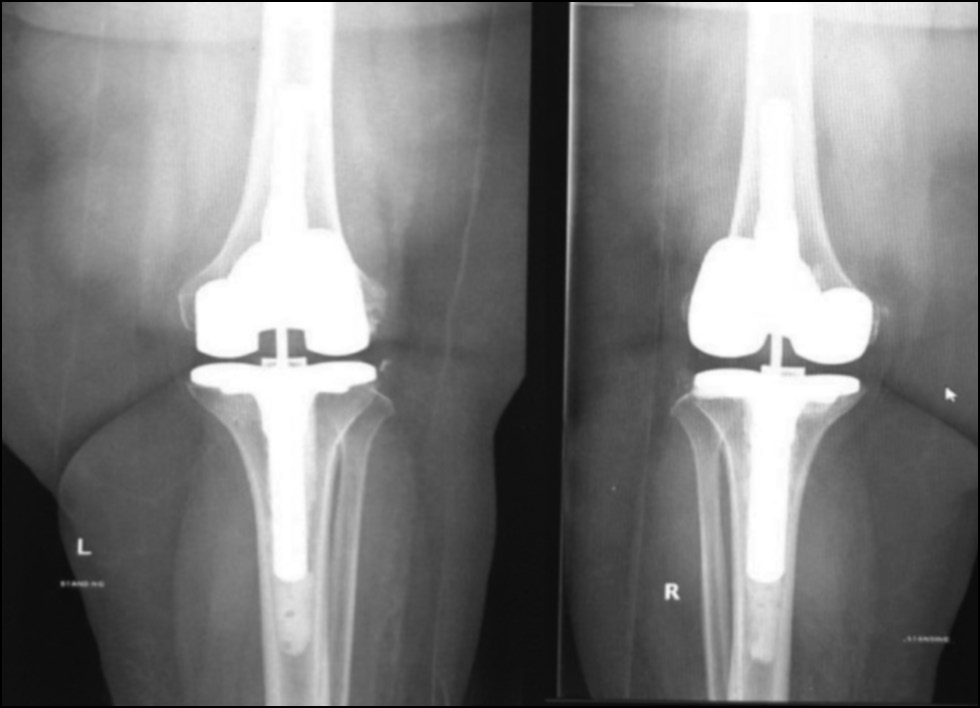

Fig. 25. Ap postoperative x-ray showing bilateral total knee arthroplasty.

Рис. 25. Послеоперационная рентгенограмма с двусторонней тотальной артропластикой коленного сустава.

Fig. 26. Lateral postoperative x-ray right and left knees showing bilateral total knee arthroplasty.

Рис. 26. Послеоперационная боковая рентгенограмма правого и левого колена, демонстрирующая двустороннюю тотальную артропластику коленного сустава.

CASE 4. PATIENT 25

Age: 65 years.

Sex: Male.

Diagnosis: Bilateral advanced knee osteoarthritis.

Procedure: Bilateral simultaneous knee arthroplasty.

Associated illnesses: No associated comorbidities.

Postoperative follow-up: No postoperative complications were encountered.

Length of hospital stay: 6 days.

Radiological assessment (Fig. 23–26)